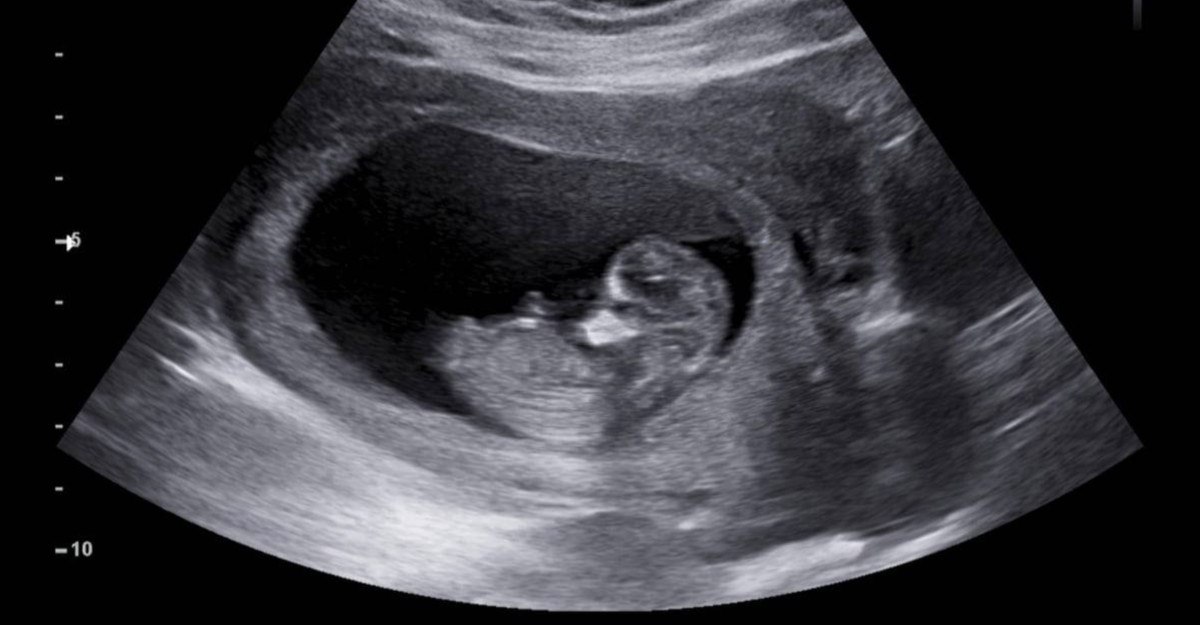

St. Jude Çocuk Araştırma Hastanesi’ndeki bilim insanları ilk rahim içi tedaviye öncülük etti.

İlacı rahim içi olarak uygulama fikri ebeveynlerden geldi ve doktorlar, anneye ilacı hamileliğinin son 6 haftasında verdi.